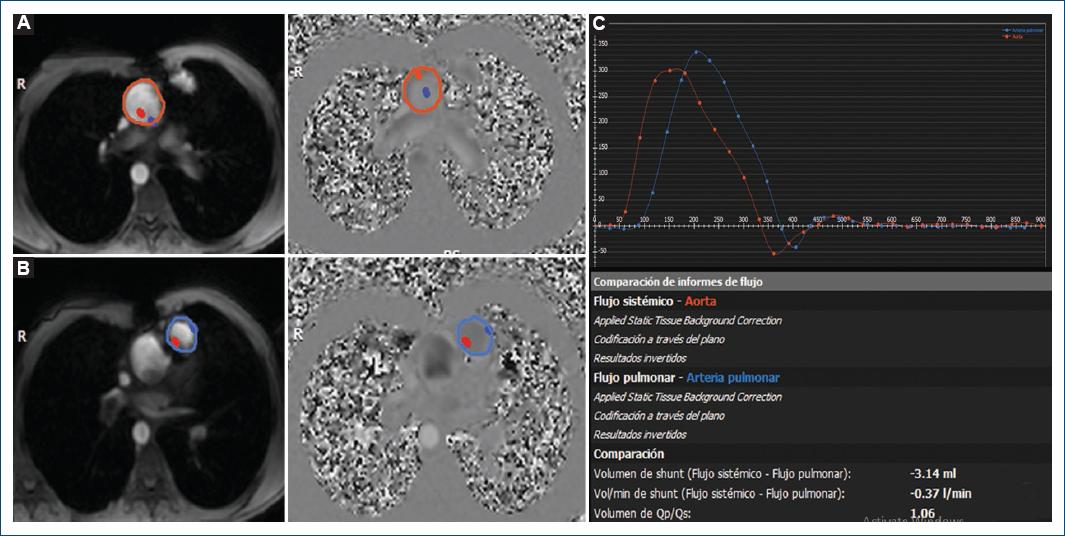

El ejemplo 3 es un paciente con tetralogía de Fallot corregida durante la infancia, portador de una válvula protésica pulmonar. Los avances en las técnicas quirúrgicas y los cuidados perioperatorios han dado como resultado una tasa de supervivencia de más del 90% hasta 20 años después de la reparación quirúrgica en pacientes con tetralogía de Fallot16. En estos pacientes se vigilan la insuficiencia pulmonar y la función del ventrículo derecho, así como la estenosis de ramas pulmonares, ya que es una complicación en estos casos. Aunque la RMC convencional (2D) es el método de referencia clínica para medir la insuficiencia pulmonar, la RMC en secuencia de flujo 4D proporciona un análisis más completo17. Se realizó un corte axial a nivel de la aorta y pulmonar (Fig. 5) con su respectiva secuencia de contraste de fase para obtener las curvas de flujo y calcular el Qp/Qs, donde se evidencia la ausencia de cortocircuito; así mismo, se realizó RMC en secuencia de flujo 4D brindándonos toda la información a partir de una adquisición (Fig. 6), con medición del flujo pulmonar de forma independiente en cada rama pulmonar, evidenciando el flujo diferencial normal a ambos pulmones. Así mismo, se corrobora este dato con el análisis mediante pathlines y streamlines que evidencian la ausencia de estenosis.

Figura 5 Ejemplo 3: paciente de 18 años con diagnóstico de tetralogía de Fallot corregida, portador de prótesis de válvula pulmonar, enviado para la valoración de la válvula protésica y cortocircuitos residuales. A: secuencias de contraste de fase 2D programadas sobre la aorta (ROI roja). B: secuencias de contraste de fase 2D programadas sobre la arteria pulmonar (ROI azul). C: tabla de cuantificación de Qp/Qs, que muestra la curva de flujo aórtico y pulmonar obtenida en la estación de trabajo con secuencia de contraste de fase (Q-Flow).